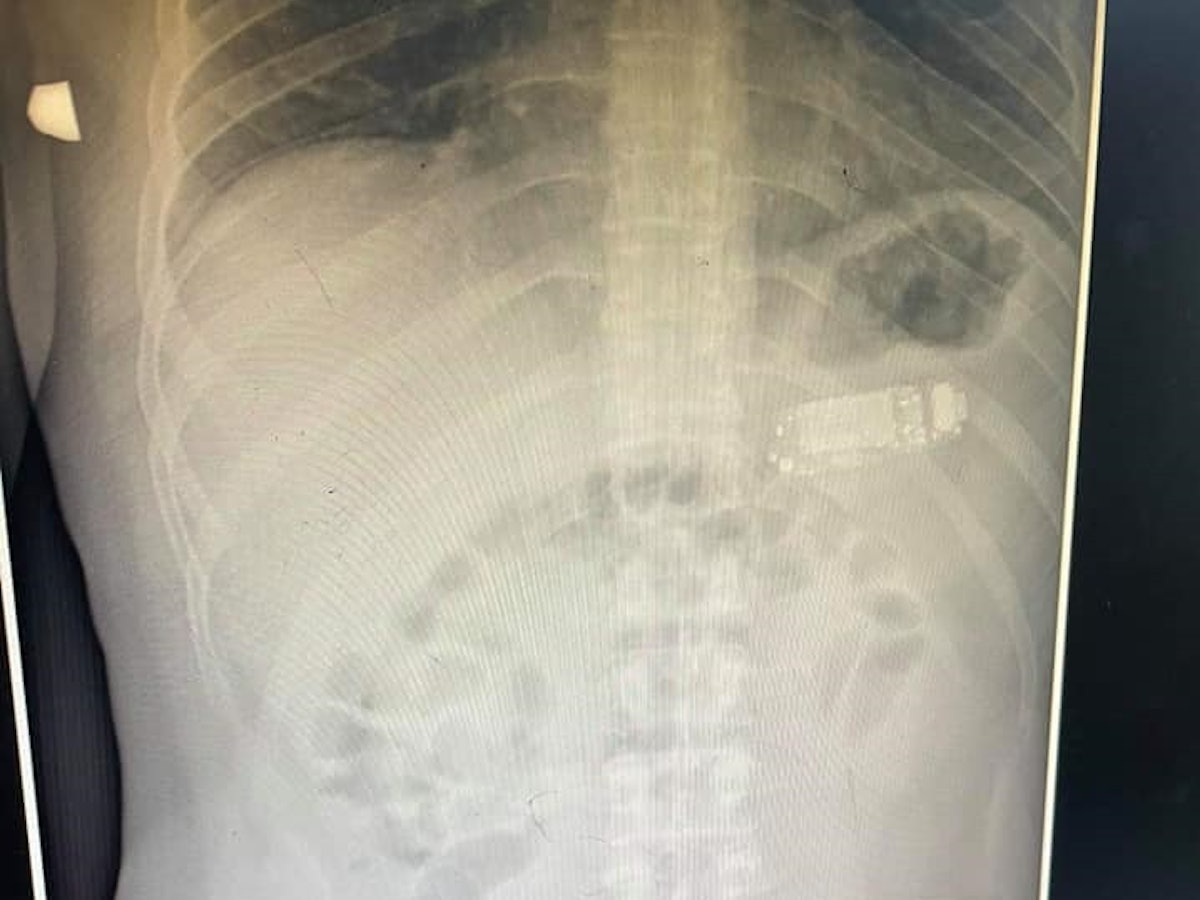

Der junge Mann kam um einen chirurgischen Eingriff nicht herum: Dem 15-Jährigen musste ein Muskel im Bereich der Geschlechtsorgane längs aufgeschnitten werden, um an das Kabel zu gelangen. Anschließend wurde das Kabel abgeschnitten, beide Enden konnten erfolgreich durch die Harnröhre herausgezogen werden.